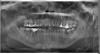

Правая шестерка. Нижняя.

Боль начинается на нижней челюсти, в районе 6. 7. 8-го зуба. а затем начинают болеть и верхние зубы.

6-ка в таком состоянии, как на снимке, очень давно. Лет 10.

Сделали снимок.

Врач предположил, что болит 6-ка. Предлагает удалить зуб и одновременно установить имплант.

Если все из-за нижней 6-ки можно ли ставить имплант сразу?

Одновременно удалять и 8-ку?

Уважаемые специалисты, посмотрите снимок пожалуйста.

Может ли другой зуб вызывать боль?